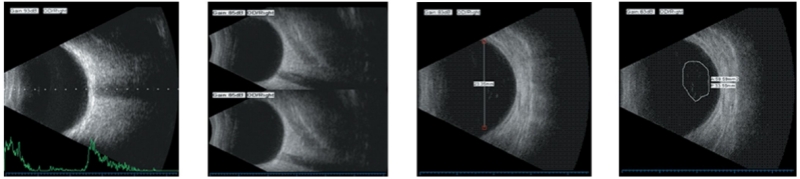

| B Scan | Frequency: 10MHz/20MHz (optional) ,Magnetic driven, noiseless Scanning Mode: Sector Scanning Magnify:Multi continuous magnification,Real-Time magnification Resolution: Lateral ≤0.3mm; Vertical≤0.2mm Geometry position precision: Lateral ≤10%; Vertical≤5% Depth:60mm Enhance the part of vitreous body and retina Gain of probe:30dB-105dB Scanning Angle:53° Gray Scale: 256 False Color: Multi colors. OCT measurement type: multigroup distances, perimeters and areas Image postprocessing: multiple curves processing, Pseudo-color processing curve Movies: 100 images movie review, AVI JPG format image output |